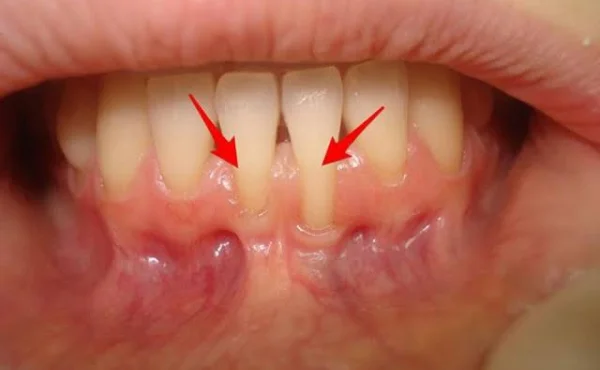

Diş eti çekilmesi, dişlerin kök yüzeylerinin açığa çıkmasına yol açarak hem estetik kaygılara hem de diş hassasiyetine neden olan yaygın bir periodontal sorundur. Bu durumu düzeltmek ve sağlıklı diş etleri ile estetik bir gülüşe kavuşmak amacıyla, modern diş hekimliğinde iki etkili yöntem kullanılmaktadır: yumuşak doku grefti ve tunnel tekniği (koroner yönlü kaydırma).

Yumuşak doku grefti, diş eti çekilmesi olan bölgede eksik olan diş eti dokusunun, hastanın kendi ağız içinden alınan veya biyolojik materyallerle desteklenen doku ile kapatılması işlemidir.